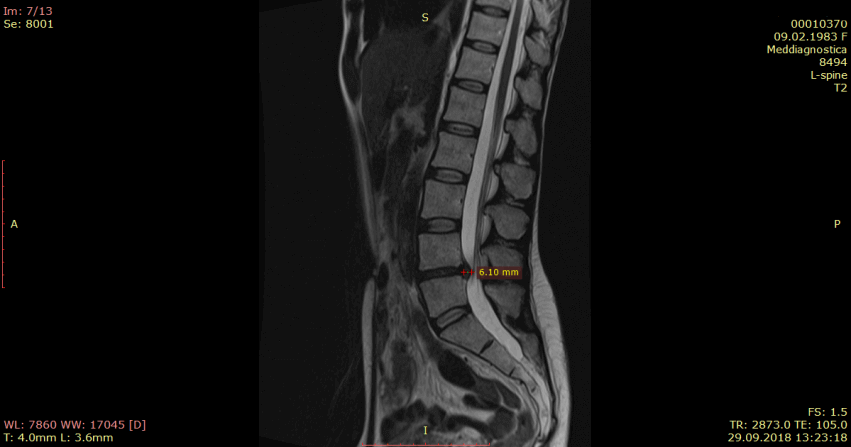

Контрольная МРТ, проведенная через 5 месяцев показала полное отсутствие грыжи диска (см. снимки Ирины ниже):

Обратите внимание на даты проведения МРТ в правом нижнем углу. МРТ исследования проведены на одном аппарате 1.5 теслы в клинике «Меддиагностика» в процессе лечения Ирины. МРТ позвоночника позволяет отследить динамику уменьшения грыжи диска.. Ирина прошла не только курс лечения, но и курс реабилитации